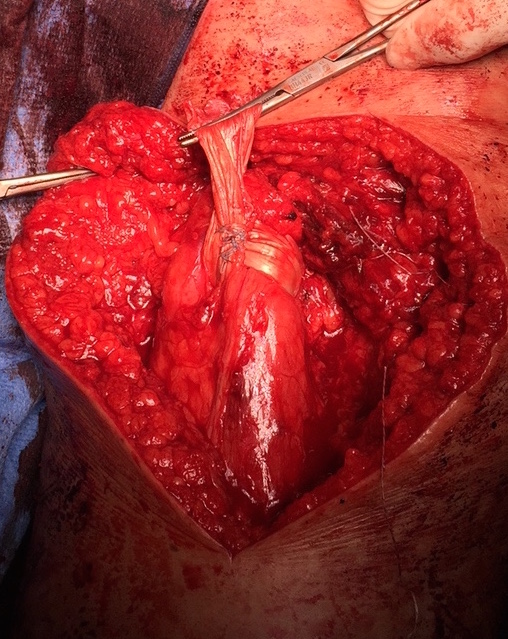

Hamstring (*) with sciatic nerve lateral to hamstring (blue vessiloop)

Identify and release proximal hamstring tendon

Stump of the conjoint tendon (*)